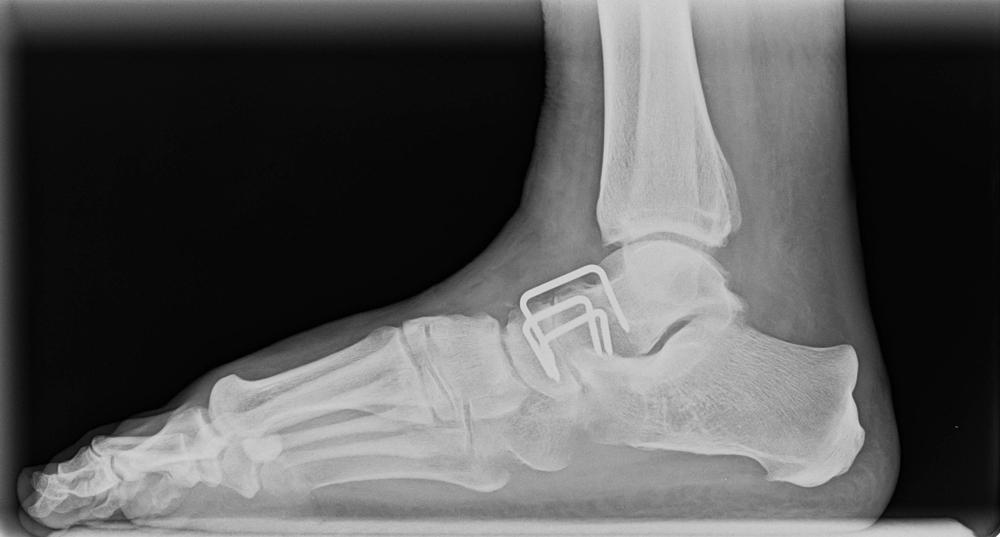

Arthrodesis adalah sebuah operasi yang merujuk pada prosedur medis untuk menyatukan dua tulang pada persendian. Dalam pelaksanaannya, dokter ahli bedah ortopedi akan meluruskan sendi yang rusak secara manual, mengangkat tulang lunak, dan menstabilkan tulang pada persendian tersebut agar bisa pulih secara bersamaan.

Umumnya, prosedur ini paling sering dilakukan untuk pergelangan kaki (ankle), kaki (foot), atau tulang belakang (spinal). Jika prosedur ini berhasil, persendian yang terdampak memang tidak bisa bergerak kembali, tetapi tulang yang menyatu pada persendian tidak akan terasa sakit.

Pada pelaksanaannya, dokter bedah akan membuat sayatan pada kulit pasien di area tulang yang terdampak. Lalu, sebuah alat pipih bernama arthroscope akan dokter masukkan ke dalam tubuh melalui satu sayatan.

Sebuah kamera melekat pada arthroscope agar dokter bisa melihat dengan jelas bagian dalam tubuh tersebut. Dokter bedah akan mengangkat tulang lunak yang masih tersisa pada persendian yang mengalami kerusakan.

Kemudian, dokter akan menghubungkan dua tulang pada posisi yang tepat menggunakan peralatan operasi sesuai kebutuhan. Dokter juga akan memperbaiki bagian tulang dan persendian yang terdampak jika perlu.